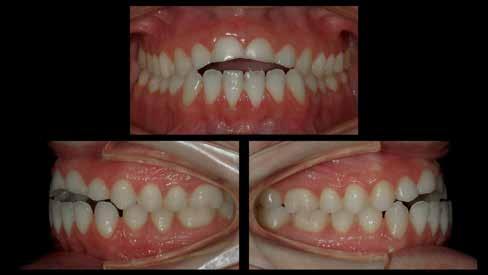

A cikkben egy fiatal nő kezelésének interdiszciplináris megközelítését foglaltuk össze, aki fogászati állapota miatt hoszszú ideje szenvedett fizikálisan és pszichésen is (1. ábra)

1. a–c ábrák: Kiindulási helyzet: fiatal páciens komoly fizikai és pszichés szenvedéssel.

A fogak extrahálása és az alveoláris plasztika teljes narkózis mellett történt meg, így teremtve ideális helyzetet a protetikai ellátáshoz. A műtéti beavatkozás után a páciens az ideglenes fogsorral távozott. Egy héttel később jött kontrollra. Nemcsak látványra változott meg nagymértékben, hanem egyértelműen magabiztosabb és önbizalommal teli volt a fellépése (12. ábra)

Az elsődleges terápiás szakasz kulcsfontosságú volt a teljes rehabilitáció szempontjából. A páciensnek nem csak szép, esztétikus mosolyt kölcsönzött, hanem életminőségének javulását is hozta (13. ábra). A Digital Denture folyamatnak köszönhetően a kezelés ráfordításai is alacsonyak voltak. A fiatal nő messzemenően boldog, magabiztos és motivált a következő lépéshez.

12. ábra: Páciensünk egy héttel fogainak extrahálása és az ideglenes fogsor azonnali behelyezése után. 13. a–d ábrák: Látványos átalakulás: kezelés előtt és után. A páciens maga hangsúlyozta ki életminőségének jelentős javulását.